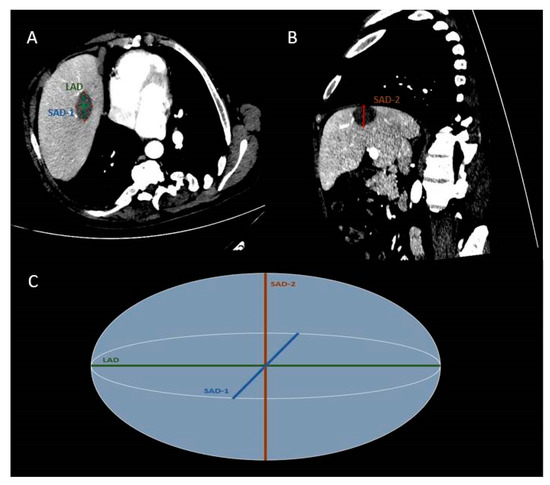

| LAD | 38.76 ± 10.24 (19–60) | 34.31 ± 9.80 (15–55) | 42.37 ± 8.08 (28–66) | 37.29 ± 7.70 (23–62) | F = 2.905, p = 0.092 | F = 31.815, p < 0.001 | F = 2.779, p = 0.100 |

| SAD-1 | 26.67 ± 8.41 (11–46) | 22.69 ± 7.80 (7–40) | 30.03 ± 7.75 (14–45) | 26.29 ± 7.58 (12–42) | F = 5.416, p = 0.023 | F = 25.067, p < 0.001 | F = 0.029, p = 0.864 |

| SAD-2 | 27.69 ± 8.78 (12–45) | 23.76 ± 8.32 (11–40) | 31.86 ± 8.02 (17–48) | 27.80 ± 7.07 (14–45) | F = 6.896, p = 0.010 | F = 16.807, p < 0.001 | F = 0.182, p = 0.671 |

| mSAD | 27.18 ± 8.26 (13.50–45.50) | 23.23 ± 7.73 (11.00–39.50) | 30.94 ± 7.14 (17–46.50) | 27.04 ± 6.74 (15–43.50) | F = 6.943, p = 0.010 | F = 27.376, p < 0.001 | F = 0.038, p = 0.846 |